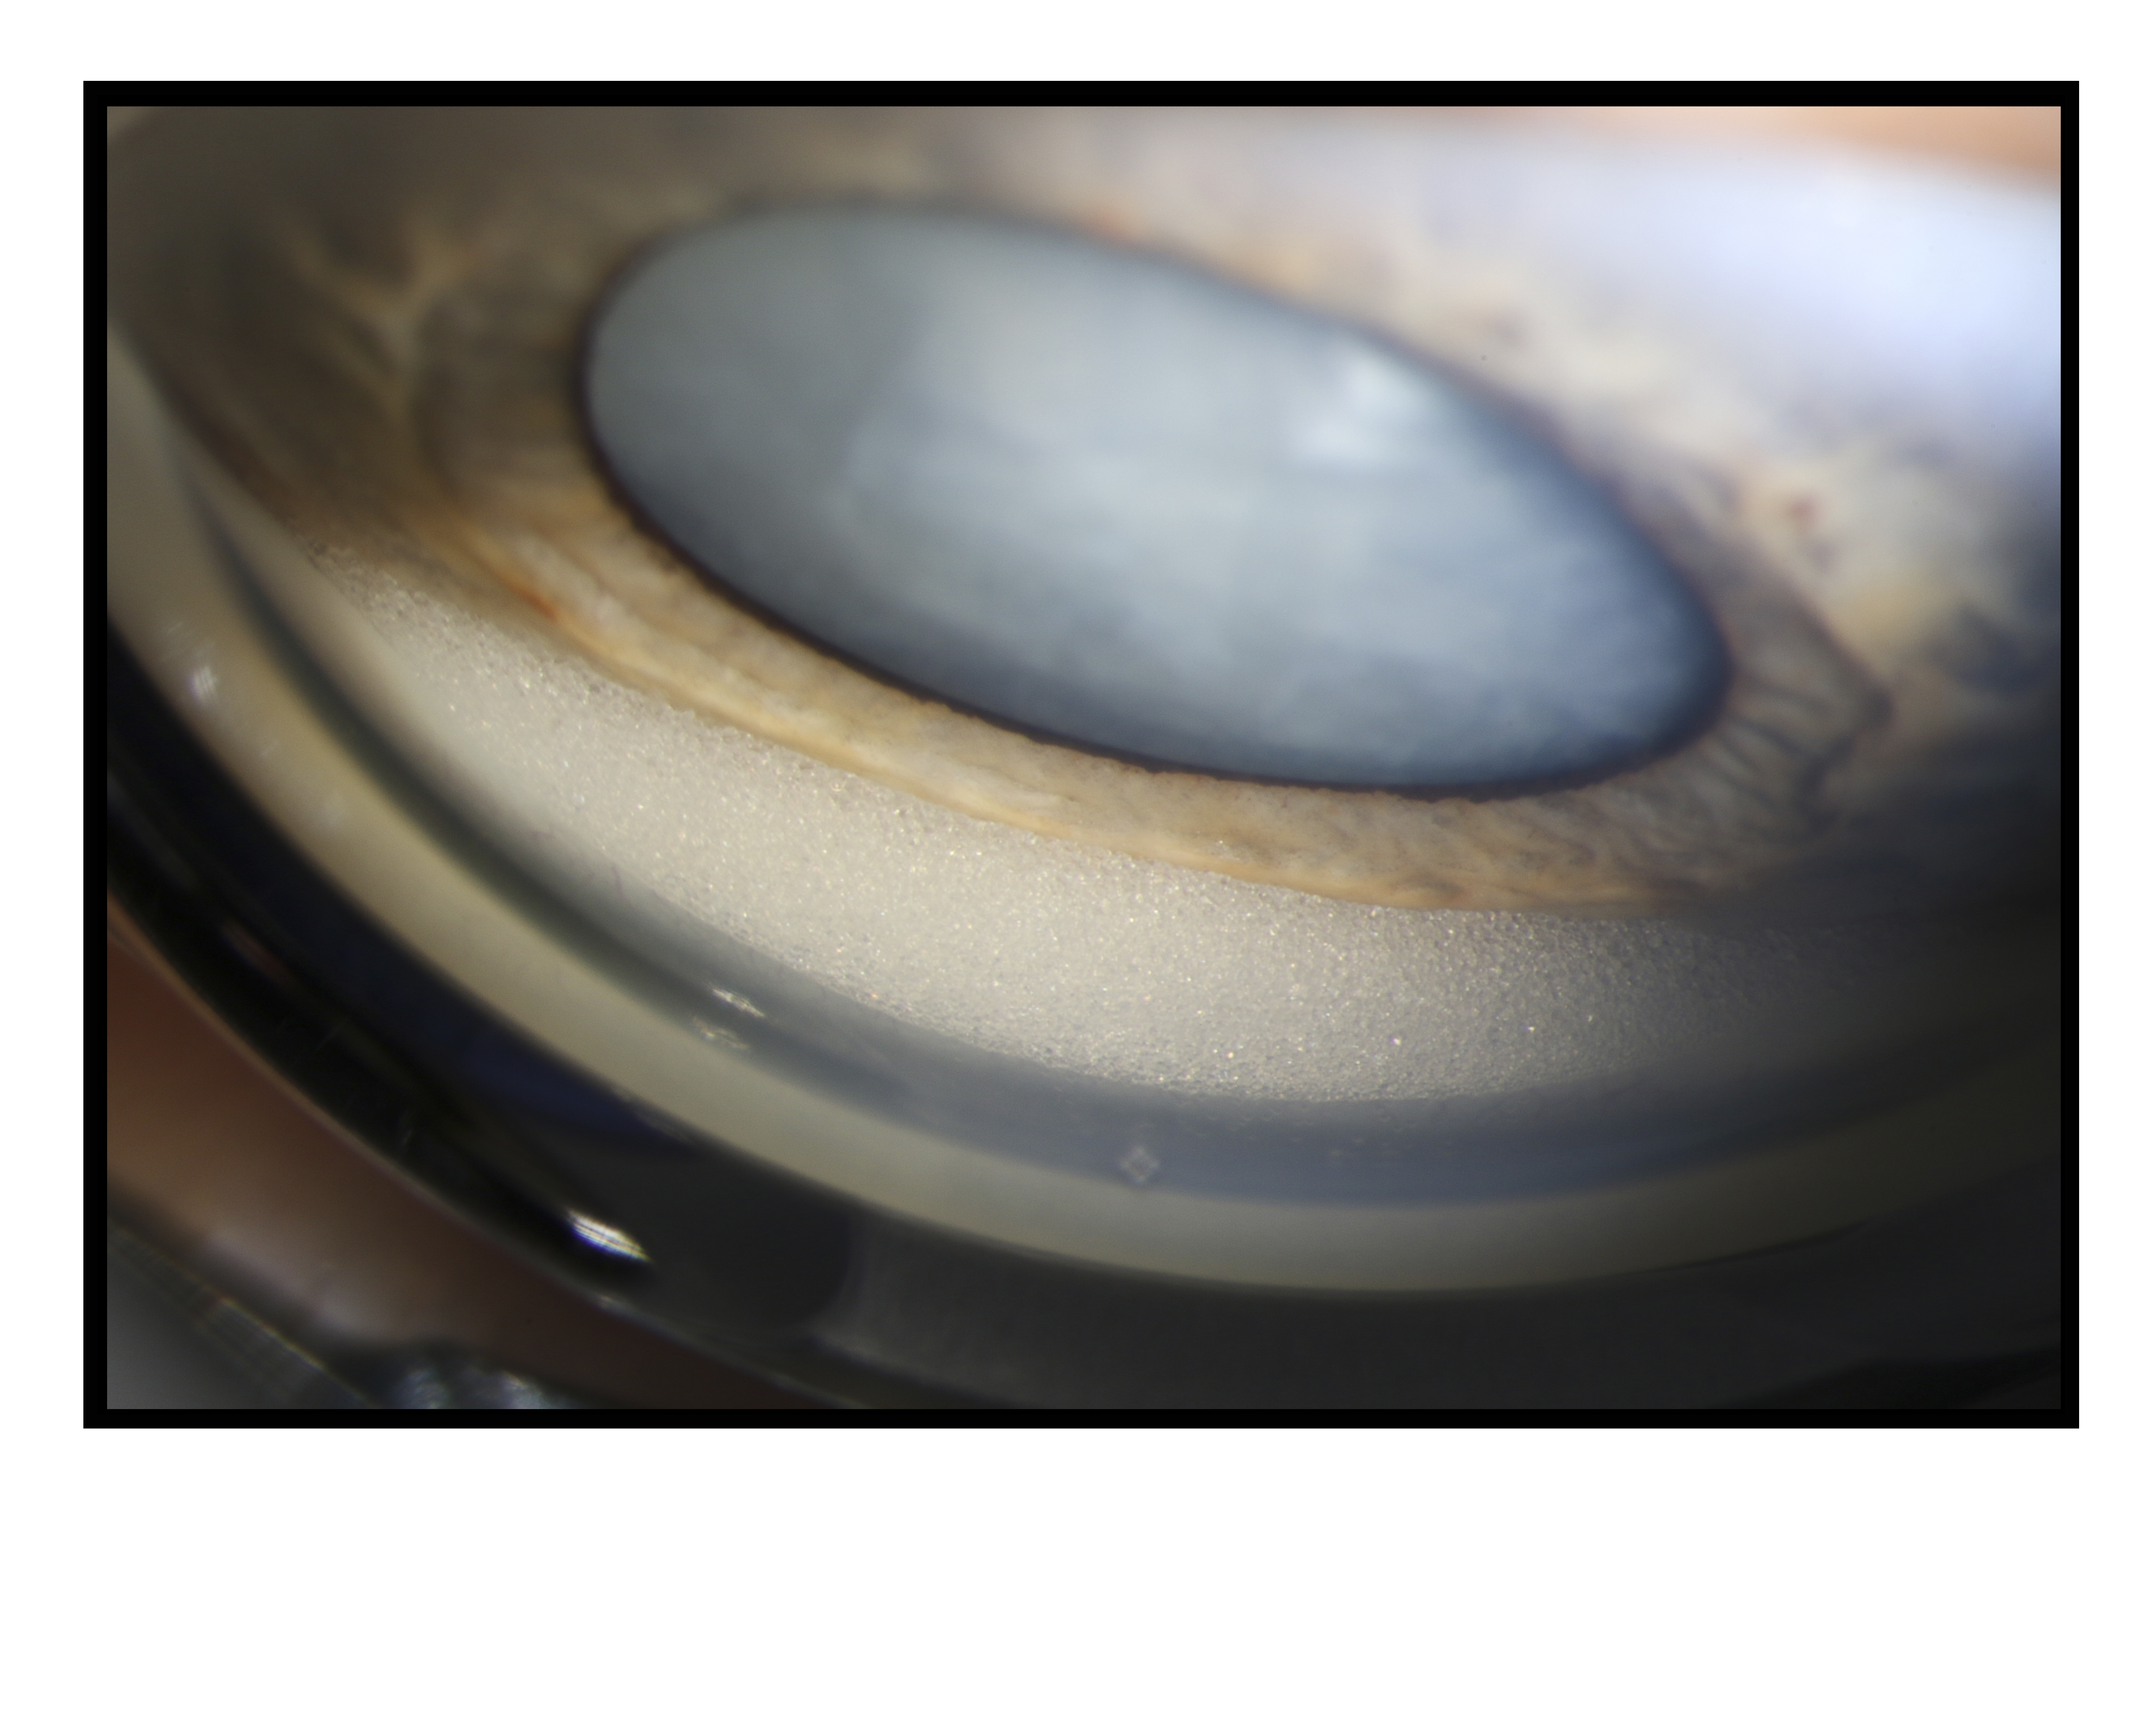

Silicone Oil in the Anterior Chamber Presented by Katie Lachut-Yevieh This photograph received First Place in the category "Gonio Photography" and was displayed in the 2024 OPS Exhibit. Filed Under Cornea OPS Photo